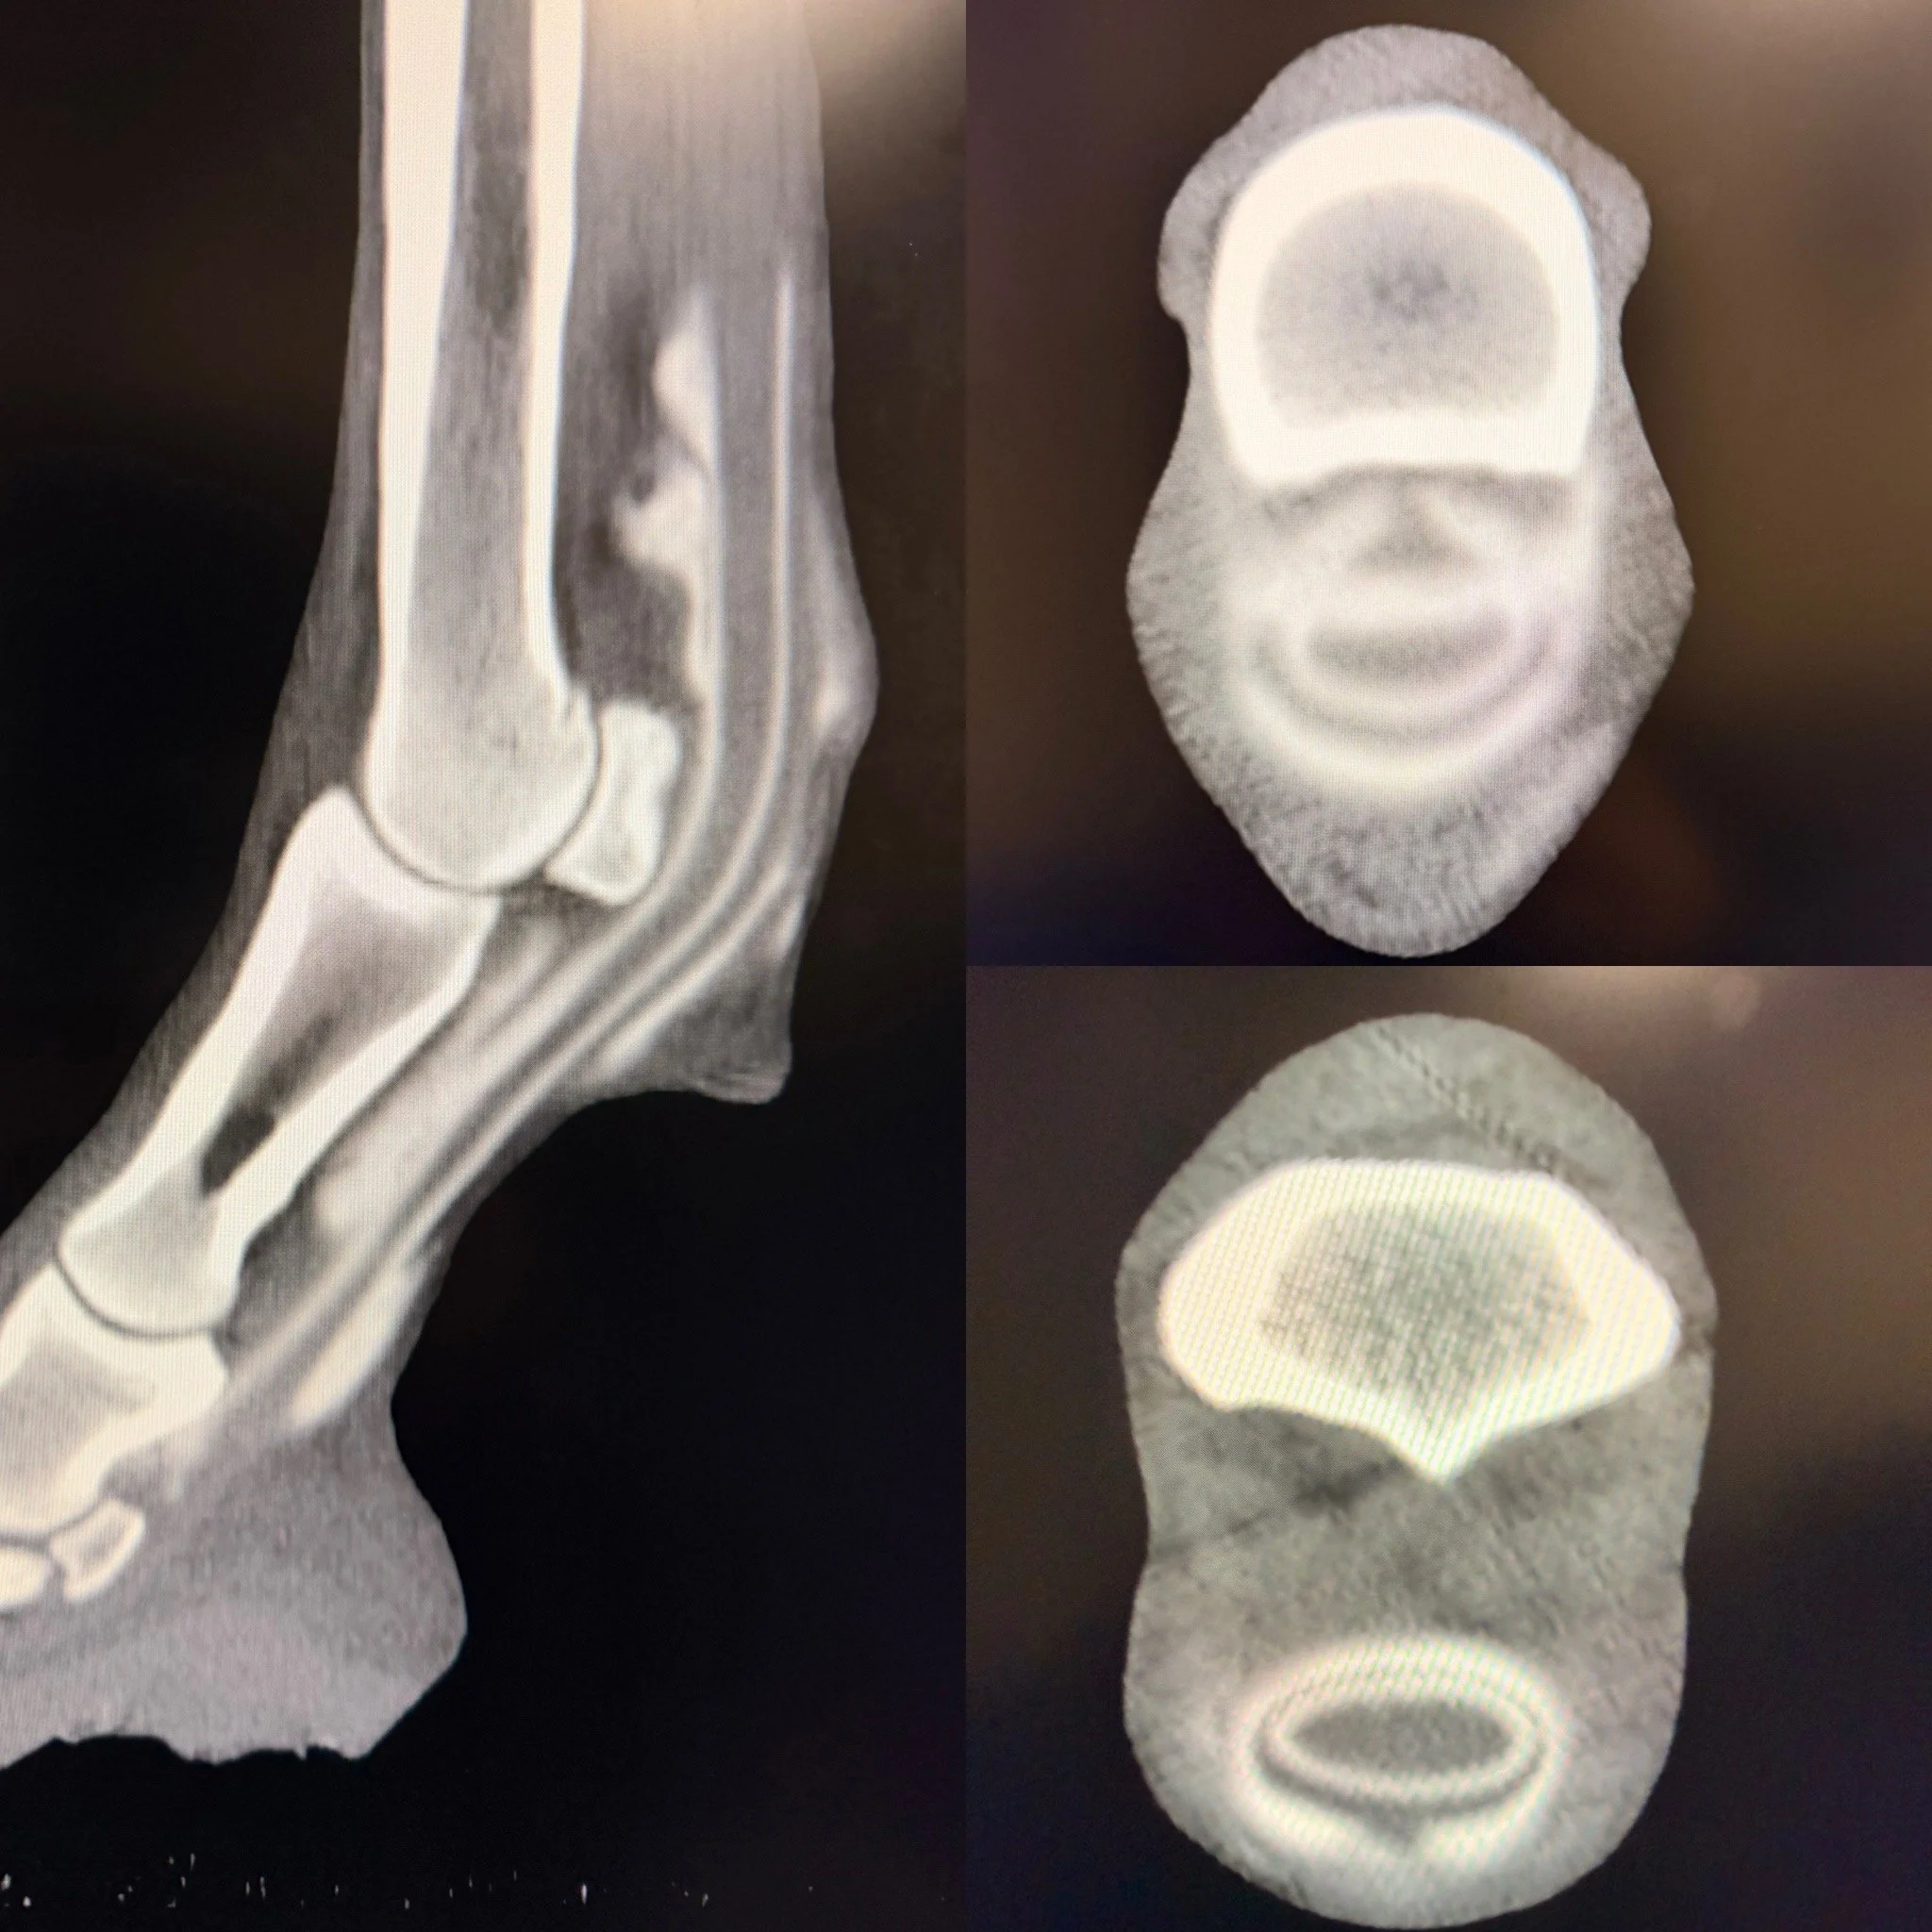

CT scan of a human ankle in lateral view, with cross-sectional images of the ankle's bones from above and below.